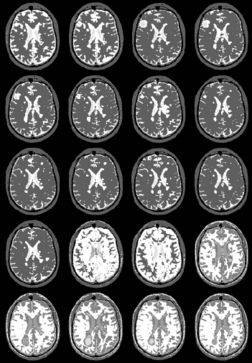

| + | {| | ||

| + | |+ '''Fig 1. EM Segmentation: Cross-Sections of Segmentations (1993)''' | ||

| + | |valign="top"|[[Image:one.jpg|thumb|252px|slice of T1 weighted mr (right temporal lobe has bad "shading")]] | ||

| + | |valign="top"|[[Image:two.jpg|thumb|252px|threshoding result]] | ||

| + | |valign="top"|[[Image:three.jpg|thumb|252px|EM result]] | ||

| + | |} | ||

The EM segmenter grew out of a collaboration between Sandy Wells, Ron Kikinis and Martha Shenton in about 1993. The goal was to get good automatic segmentations of white matter and gray matter from T1 weighted MRI. The biggest difficulty was the intensity inhomogeneities, or "shading", artifact in the images that was due to the MRI scanner used for research at that time. The effect of the artifact was that a single threshold could not be used to separate white matter and gray matter.

We chose the Expectation Maximization (EM) algorithm, a statistical estimation method that is used when some data is considered to be "missing". The result was an iterative algorithm that alternates between two steps.

In the "E" step, the probability of the tissue label at each voxel is estimated, given the image data and the current estimate of the intensity artifact.

In the "M" step, the intensity artifact is re-estimated, given the image data and current estimate of the tissue label probabilities.

The EM segmenter proved to be very robust to shading artifacts, but in addition, it was also robust to "inter-scan inhomogeneities". With previous classification approaches to segmentation, "training" was needed on a per-scan basis, because of intensity changes from scan to scan.